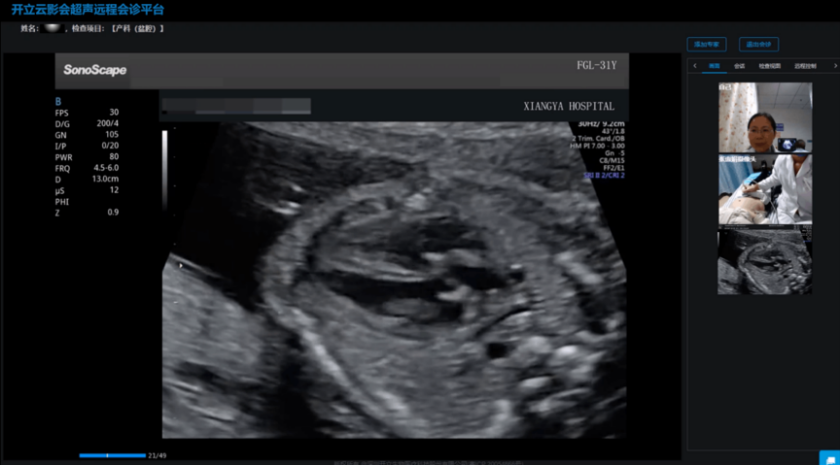

随着“云影会”远程医疗和5G技术的不断应用,智能超声医学影像正迎来前所未有的发展机遇。从2022年开始,中南大学湘雅医院率先启动了产科超声5G远程会诊,并覆盖了湖南省88家医院,让湘雅医院多学科优质资源下沉,疑难杂症快速响应支援,合理针对不同的孕产妇救治需求提供有效救治。打破时空限制,人工智能辅助诊断系统正在成为远程会诊和分级诊疗的重要支撑,为医疗行业均质发展提供数字化基础。

在中心医院专家的指导下,乡镇卫生院的超声医生能够获得更好的影像,并通过视频连线获得即时的专业指导和建议。同时,上级专家可以远程指导下级医院编写、审核超声图文报告。这种“面对面”的远程教学,不仅提升了基层医生的诊断技能,更增强了他们的工作信心和职业成就感,可以为乡村患者带来更加精准、可靠的诊断结果。